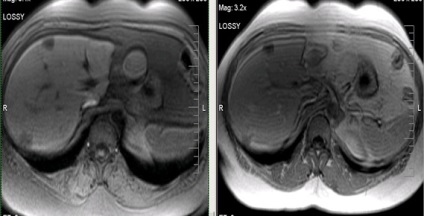

Hepatocelluláris rák (az US - hemangioma).

Hepatocelluláris rák (infiltratív formájában), a másodlagos lymphadenopathia.

Cholangiocelluláris rák (kolangiokarcinóma).

Tulajdonságaiból adódóan az emberi test keringési, a vena portae rendszer rendelkezésre állása, metasztázis különböző tumorok a máj nagyon természetes. A leggyakrabban áttétet a máj gyomor tumorok, vastagbélrák, hasnyálmirigyrák, tüdőrák és emlőrák.

Több májáttétek.